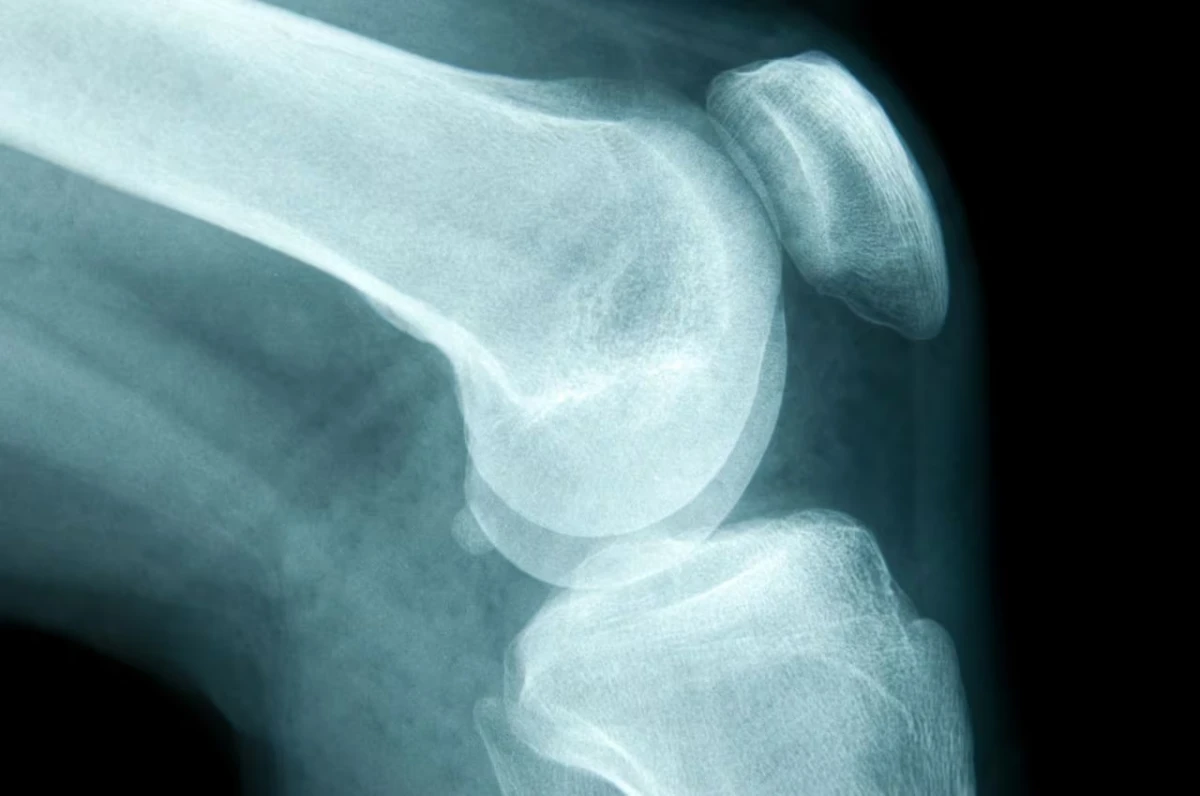

Este cáncer puede originarse en cualquier hueso del cuerpo, pero en la mayoría de los casos afecta la pelvis o los huesos grandes de los brazos y las piernas, precisa el instituto de investigación Mayo Clinic. Desde el organismo también señalan que sólo representa a menos del 1% de todos los tipos de cáncer.

- Osteosarcoma: generalmente, se desarrolla entre los 10 y 19 años de edad y ocurre más comúnmente en la rodilla o en la parte superior del brazo.

Cáncer en los huesos: cuáles son sus principales factores de riesgo y qué síntomas aparecen primero (Getty Images)